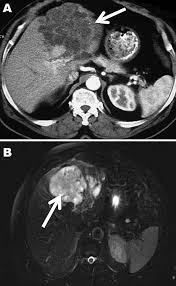

Chest computed tomography of case 2, showing in filtration with an air bronchogram in the left lower lobe and interlobular septal thickening around the infiltration.

Chest computed tomography of case 2, showing in filtration with an air bronchogram in the left lower lobe and interlobular septal thickening around the infiltration. 1.熱性疾患の鑑別疾患にオウム病を入れる オウム病は、呼吸器症状を欠く発症もあり得る。 また、市中肺炎の経験的治療の中で、ペニシリンや セフェム系抗生剤に反応しない場合には、熟考すべ きである。 2.鳥との接触歴を詳細に聴取する ― オウム病はオウム病クラミジア chlamydophila (chlamydia) psittaci を病原体とし,オウムインコ類など愛玩用の鳥からヒトに感染し,肺炎などの気道感染症を引き起こす疾患です。. Z + wheel + ↓:縮小: オウム病はオウム病クラミジア( chlamydia psittaci 以下 c.